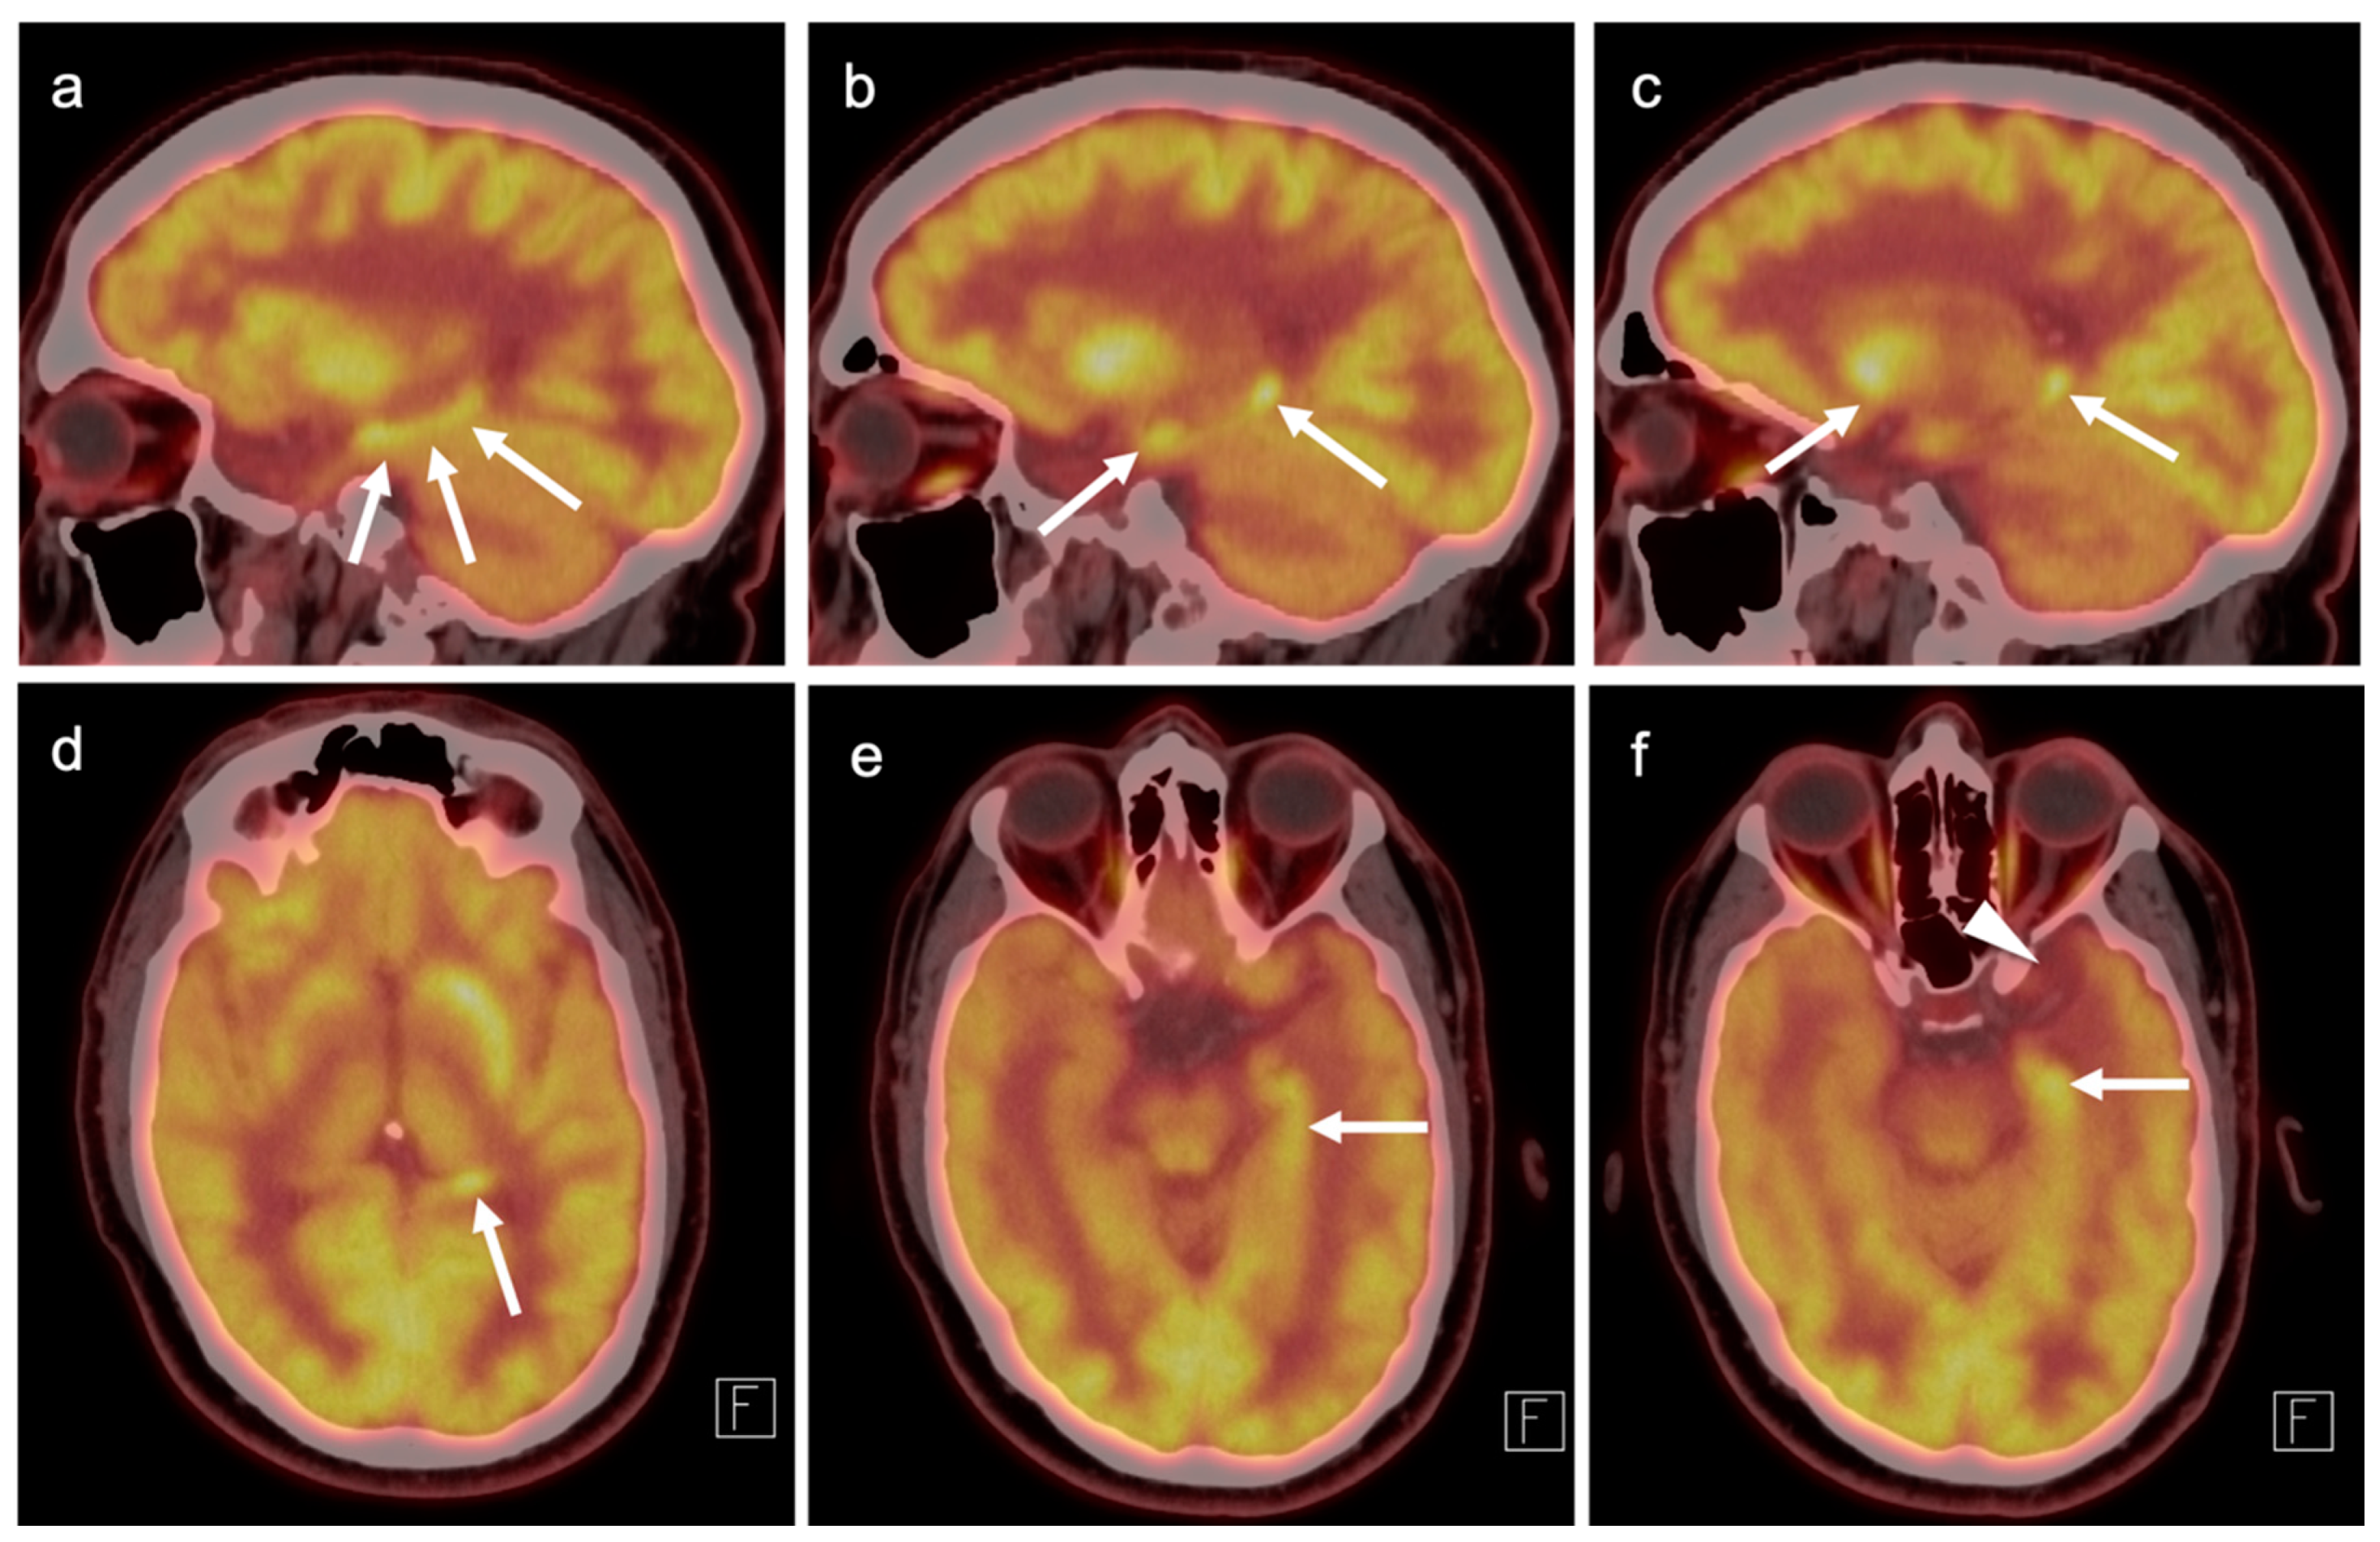

3.5. Brain Metastases

3.6. Response to Therapy